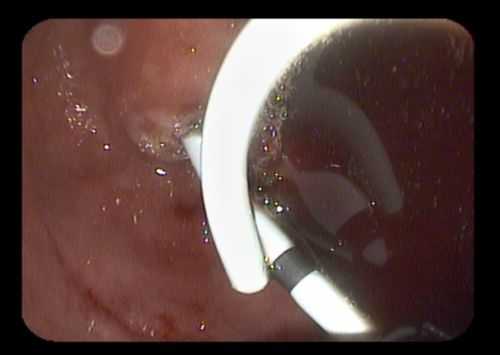

5. Установка трехлепесткового стента MTW таким образом, чтобы конец, содержащий два лепестка, оставался в просвете кисты (рис. 3, 4). Рис. 4. Эндоскопическая цистогастростомия с установкой в кисту трехлепесткового стента MTWE. Рис. 3. Эндоультразвуковое сканирование псевдокисты поджелудочной железы после цистотомии (в просвете определяется катетер) (пациент 1).

Затем под контролем рентгеноскопии в полость кисты вводится струна-проводник для установки пластикового стента (double pigtail) диаметром 10 Fr и длиной 10 см. Осуществляется рентгенологический и ультразвуковой контроль: он подтвердил, что дистальный конец стента располагается в просвете кисты, проксимальный - в луковице двенадцатиперстной кишки (рис. 5 в, рис. 6). При эндоскопическом осмотре оценивается область сформированного соустья для исключения кровотечения (рис. 7).